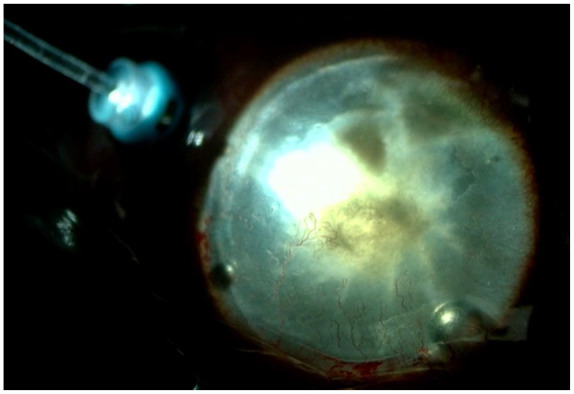

Congenital aniridia is a rare genetic eye disorder often associated with PAX6 gene mutations, leading to complex ocular manifestations, including aniridia-associated keratopathy (AAK) and cataracts. The surgical management of cataracts in these patients is particularly challenging due to severe corneal opacities, which obscure key surgical steps such as capsulorhexis and phacoemulsification. This report presents two cases of congenital aniridia with severe AAK, in which chandelier retroillumination-assisted cataract surgery was employed. This technique, typically used in vitreous surgery, provided enhanced visualization of the lens through posterior segment illumination, facilitating successful cataract extraction and intraocular lens implantation. Both patients showed significant postoperative improvement in visual acuity. These cases demonstrate the feasibility and effectiveness of chandelier retroillumination-assisted cataract surgery in patients with congenital aniridia complicated by severe corneal opacity.